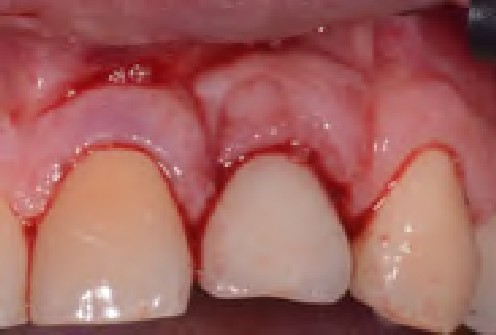

The entry of inflammatory cell infiltrate into the connective tissue (Figure 1 and Figure 2) differentiates peri-implantitis from peri-implant mucositis.1 Unlike a natural tooth—where periodontal fibers, transepithelial fibers, and gingival fibers absorb this exudate—none of these fibers are present around an implant (Figure 3). This allows the inflammatory cell exudate to directly enter the bone, resulting in bone loss and concomitant soft-tissue loss (Figure 4).1

Fig 1. In the pathogenesis of peri-implantitis, inflammatory cell infiltrate enters the connective tissue.

Figure 1

Fig 2. Inflammatory cell exudate enters right into the bone.

Figure 2